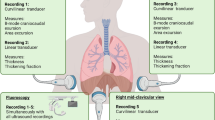

The participants were asked to perform five different respiratory procedures: three respiratory maneuvers (Apnea, Valsalva, and Mueller) and two different respiratory patterns (tidal ventilation during quiet breathing and hyperventilation), as described below. Mueller and Valsalva maneuvers were considered as a physiological model to investigate effects of the sustained contraction of intercostal muscles, since during these conditions no lung volume changes are allowed because of a closed mouth and clipped nose. Before starting the study, all subjects were appropriately trained to perform the required respiratory procedures by one of the authors (D. G. B.).

Ultrasound examination was performed on both sides during each phase by an expert critical care physician proficient in critical care ultrasound (D. G. B.), and all imaging was stored.

Respiratory maneuvers

Tidal ventilation at quiet breathing: Initially, the volunteers were asked to breathe quietly to allow the operator to identify the “bat sign” and achieve the correct angle of insonation (Fig. 1A).

Apnea: Subjects were asked to hold their breath for 10 s while keeping the intercostal muscles relaxed and inhibiting diaphragmatic activity.

Mueller maneuver (Fig. 1B): Subjects were asked to expire forcibly through the mouth, after exhalation of normal tidal volume, to residual volume and to maintain it with a clipped nose. As soon as ultrasound imaging was stabilized, the volunteers performed a sustained maximal inspiratory effort while their mouth closed and nose clipped (Mueller maneuver).

Valsalva maneuver (Fig. 1C): Subjects were asked to inspire rapidly close to total lung capacity and maintain this volume actively for 2–3 s; then, they performed a sustained maximal expiratory effort while their mouth closed and nose clipped (Valsalva maneuver).

Hyperventilation: Subjects were asked to take deep and rapid breaths to simulate polypnea.

After each maneuver and before performing the next one, the subjects were allowed to recover by breathing quietly for 2 min at least. The sequence was performed twice on both sides of the chest wall.

Ultrasound assessment and acquisition

LUS was performed while the subjects were seated on a chair with a back support to minimize trunk motion and enable the operator to maintain a steady insonation angle during the imaging acquisition.

The MyLab Five Esaote Ultrasound System (Esaote SpA, Genoa, Italy) was used, equipped with a high frequency 4–13 MHz broadband linear probe, well suited for sonographic examination of pleural line and parasternal intercostal muscles.

Imaging acquisition was obtained by placing the probe longitudinally along the midclavicular line and perpendicular to two consecutive ribs, at the level of the 3rd to the 4th intercostal spaces. This scan offers a good view of the ribs, intercostal muscles, and pleural lines (Fig. 1A). When the correct position of the probe with proper image acquisition was achieved, the operator registered and saved a 10-s video clip in B-mode for each side and two sequences of six consecutive breaths in M-mode during each respiratory maneuver. Videotapes and images were all stored on a memory disc by the principal investigator (D. G. B.).

Ultrasound interpretation and bias assessment

The same researcher (D. G. B.) who performed ultrasound examinations renamed videos and images saved based on a random sequence, making it impossible to trace the corresponding maneuver from the file name. The process was repeated twice so that two groups of files, A and B, were finally obtained, in which the same imaging was stored under different names and sequences.

Three researcher experts in critical care ultrasound (A. C., C. S., F. C.), who were blinded to the file encoding system, examined group A first and group B 15 days later. During each evaluation session, first, each rater was asked to assess whether lung sliding and lung pulse were present in each B-mode video, integrating it with the corresponding M-mode imaging and then without interacting with other investigators. The access to the related M-mode imaging was allowed only after that the three raters had sent the final assessment based on B-mode to the principal investigator (D. G. B.). Then, the assessment based on the integration of B-mode videos and M-mode images was registered and analyzed separately from the assessment based solely on B-mode. Before starting the study, the three examiners agreed on the criteria for lung sliding and lung pulse presence after two meetings.